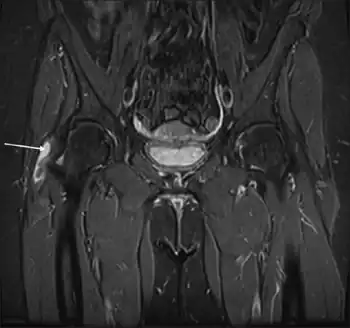

X-rays, ultrasound and magnetic resonance imaging may reveal tears or swelling. But often these imaging tests do not reveal any obvious abnormality in patients with documented GTPS.[2]